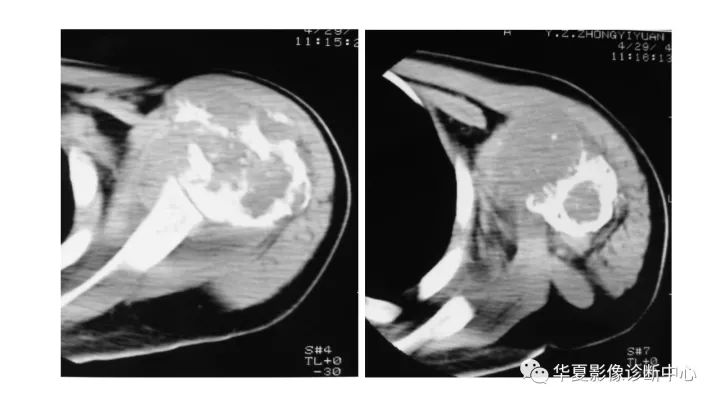

肱骨上段软骨肉瘤1例X线CT及MR影像表现

【病例】肱骨上段软骨肉瘤1例X线CT及MR影像表现